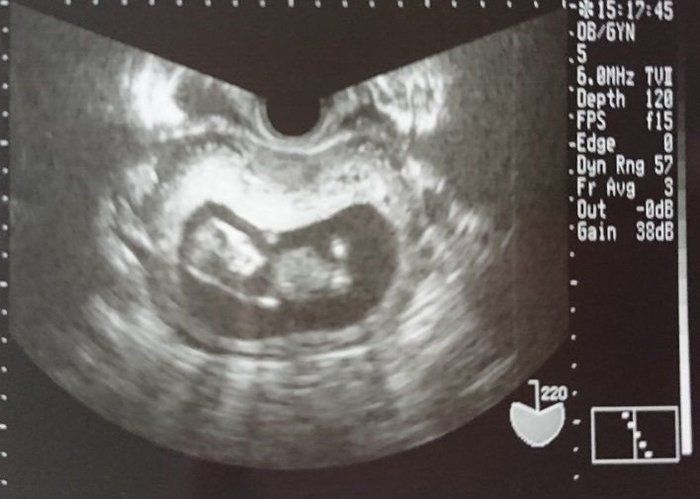

命の始まりは神秘的!2D・3D・4Dのエコー写真で見る「私と赤ちゃんの実録260日」 -

緊急帝王切開で誕生。エコー写真で綴る息子と過ごした252日 -